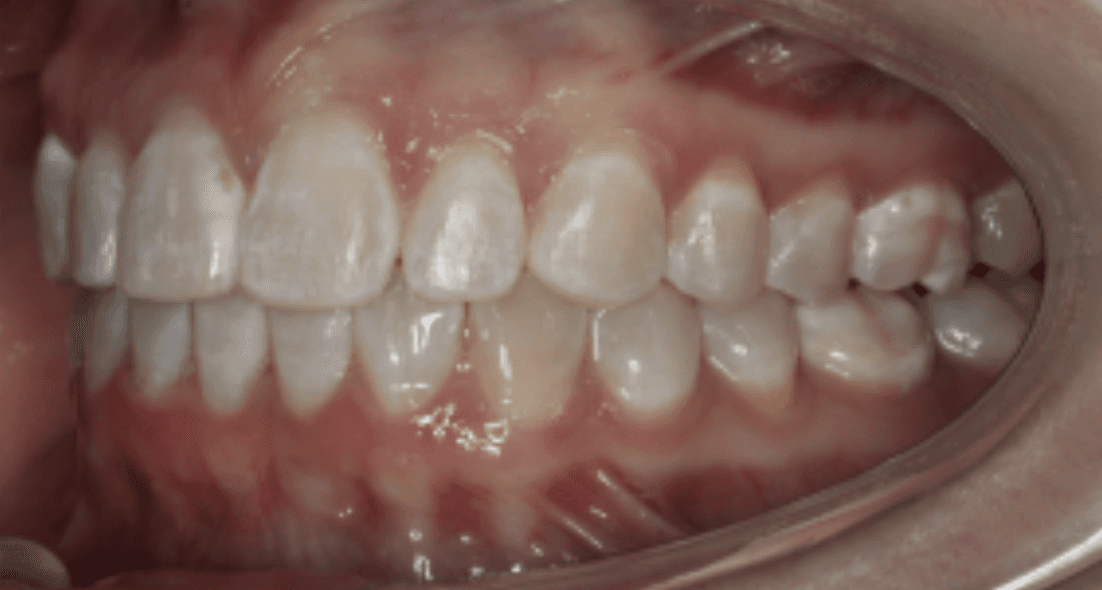

Diagnosis: Deep bite, lower anterior crowding, rotated upper lateral, arch misalignment, wear on teeth from grinding

Final results

INTRAORAL